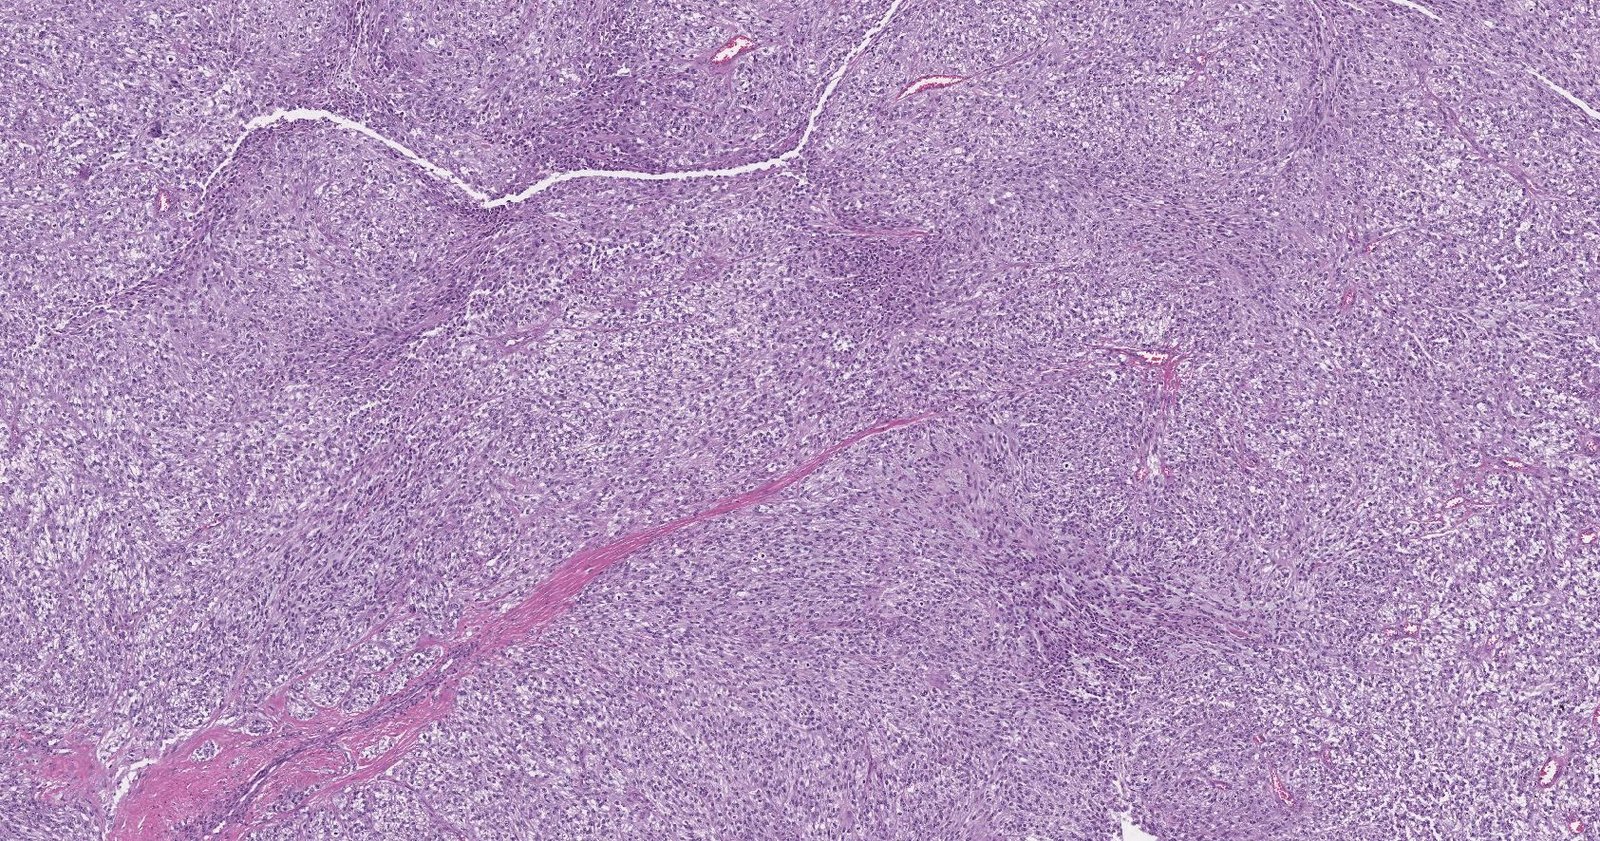

Case: TendonMass

Final Diagnosis: